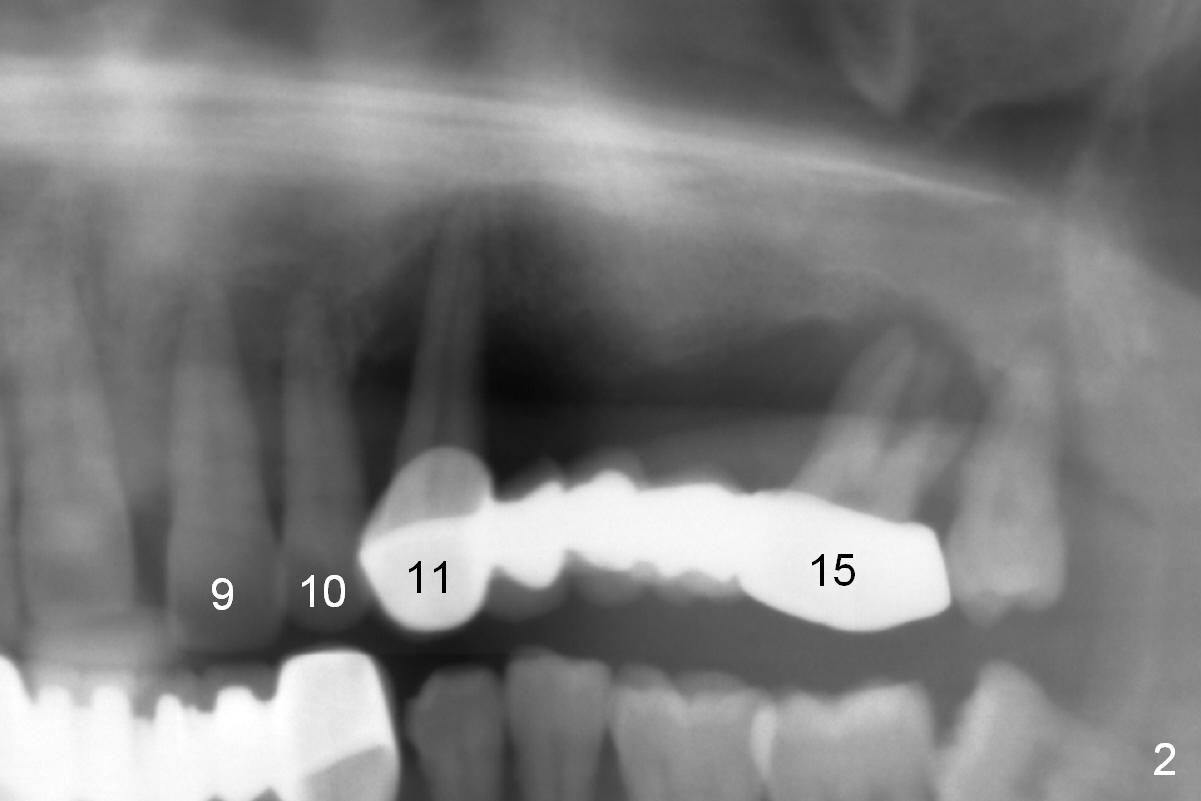

A 45-year-old man has advanced periodontitis and bruxism (sufficient remaining bone height, Fig.1).  Full mouth restoration will be done by quadrant with preservation of a few of relatively healthy teeth.  The 1st quadrant to be treated will be the upper left (Fig.2).  The teeth #9-11 and 15 will be extracted (Metronidazole) with immediate implants.  A delayed implant will be added at #13 for #11-15 bridge (Fig.4).  In addition to the large radiolucency around the roots of #9 and 10 (Fig.3 red dashed line), the gingiva at #11 and 15 is excessively thick (red arrows).  For example at #11, a long implant has to be placed a little more outside the bone (Fig.4 green area), since the longest cuff of the abutment (red area) is 5 mm for UF implant system.  The longer the cuff, the less amount of the implant will be outside the bone with less chance of periimplantitis.  When the coronal implant threads are exposed, a large amount of bone graft has to be placed (Fig.4 yellow circles).